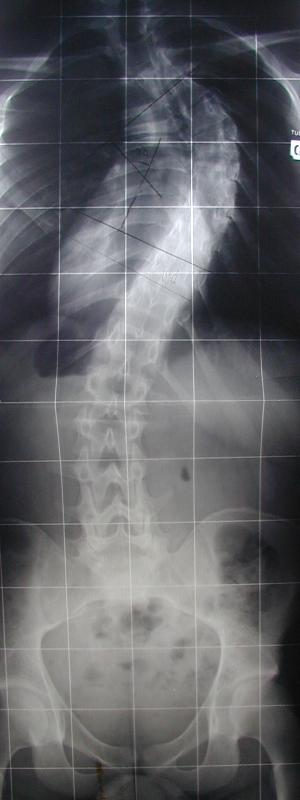

3 - atteinte des os : scoliose

radiographie collège Jules Renard 53000 Laval

Cette radiographie représente :

une colonne vertébrale déformée

un individu en position couchée

une fracture de la colonne vertébrale